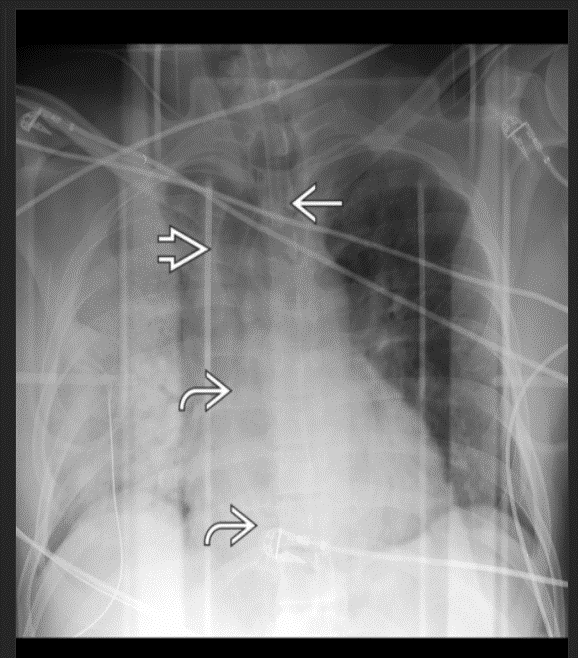

Esophageal intubation